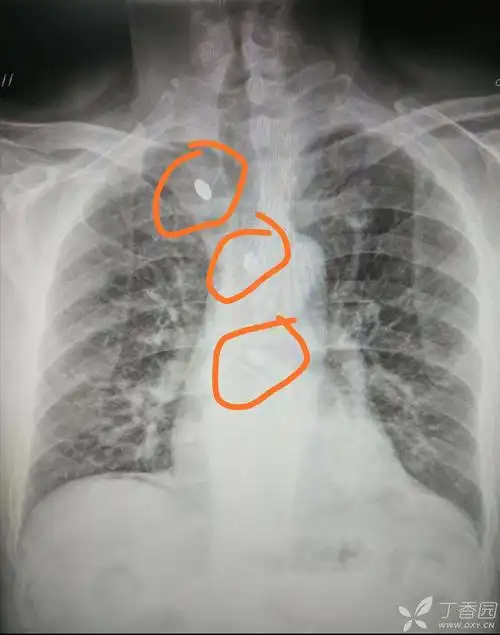

【影像读片】提供胸部ct,请高手们给出看法

【读片】看看这几张胸部ct片(无病史只看片) [病例帖]

男,56岁,右则胸痛1月余,胸片和ct

第2日胸部ct如下